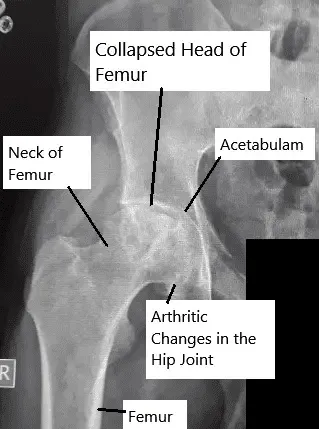

La articulación de la cadera es una articulación esférica formada por la cabeza femoral (bola) y el acetábulo (cavidad). La cabeza femoral recibe su riego sanguíneo a través de pequeñas arterias que discurren a lo largo del cuello del fémur. Cuando estas arterias se interrumpen o comprimen, el flujo sanguíneo se detiene, lo que provoca la muerte ósea de la cabeza femoral. Con el tiempo, la articulación pierde su forma redonda, lo que provoca dolor y rigidez.

Radiografía que muestra necrosis avascular de la articulación de la cadera.

- Las radiografías pueden parecer normales en las primeras fases, pero más tarde muestran colapso óseo y superficies articulares irregulares.

- Estadio IV: colapso avanzado de la cabeza femoral y artritis de la articulación de la cadera.